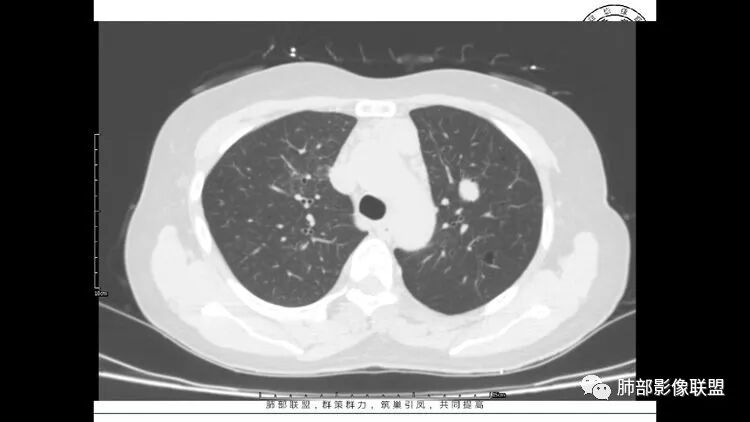

胸CT:1.双肺多发囊性变,以中下肺为主,病变边缘可见肺动脉,部分囊内可见分隔及肺动脉,双下部分肺野周围可见小叶中心结节及树丫征。

2 左肺上叶尖后段 右肺上叶前段 右肺下叶外基底段 结节影,边界清楚,可见柔软毛刺,左肺下叶后基底段混合密度影。

3.纵隔淋巴结肿大?,以主动脉弓为界向上向下增大。

患者中年女性,因右眼红痛1天就诊。胸CT:双肺多发囊性变及结节影,囊以中下肺为多,部分囊内可见分隔及肺动脉,结节部分为实性,部分为混合性,边缘光滑,未见明显毛刺、棘突、胸膜牵拉及血管集束征象。双中下可见支气管扩张及树丫征。淋巴结无明显肿大。综合考虑:一元淋巴细胞间质性肺炎。多元鉴别肺腺癌并转移等恶性病变。

双肺下叶分布为主的间质改变(磨玻璃影、小叶间隔增厚)、散在气囊影(常有血管贴边)、边界不清小结节